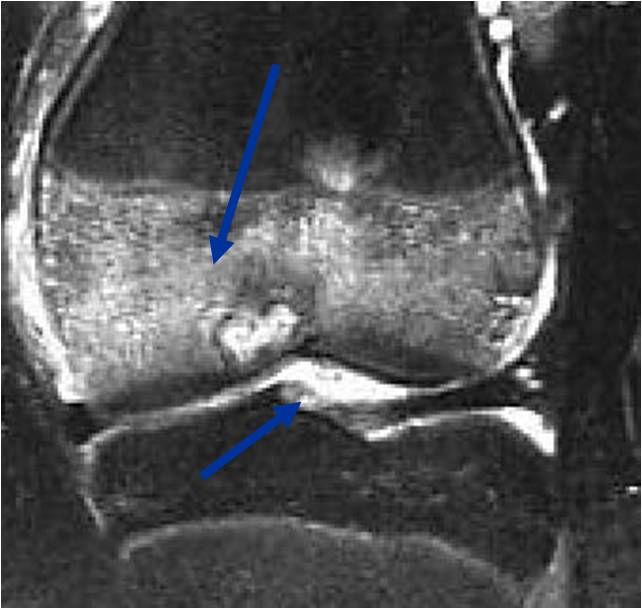

- (MRI appearance)

- Geographic, well circumscribed lesion in the epiphysis

- Intermediate Signal on T1

- High signal on T2 mixed with low signal areas (low signal areas proposed to be secondary to lysosomal content of highly cellular areas)

- Fluid/Fluid levels demonstrated in tumors that have undergone ABC change (aneurysmal bone cyst change)

- Extensive Surrounding edema is common

- Joint effusion in 30-50% of cases